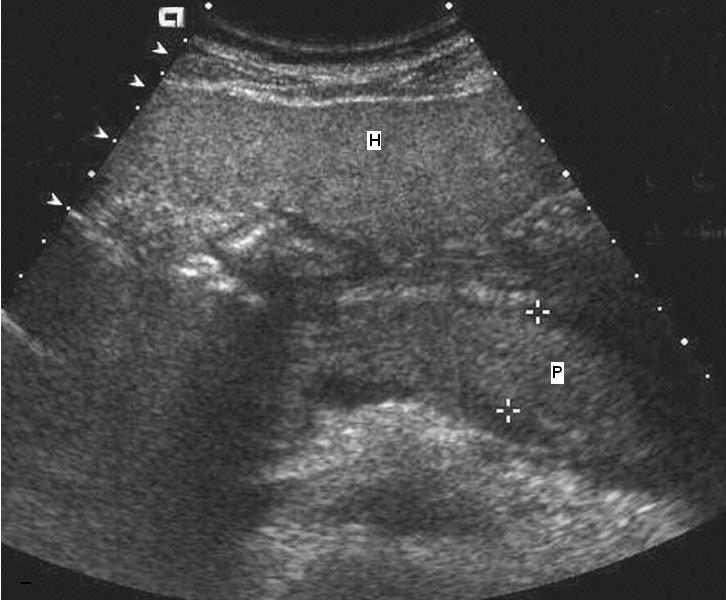

Pancreatitis aguda